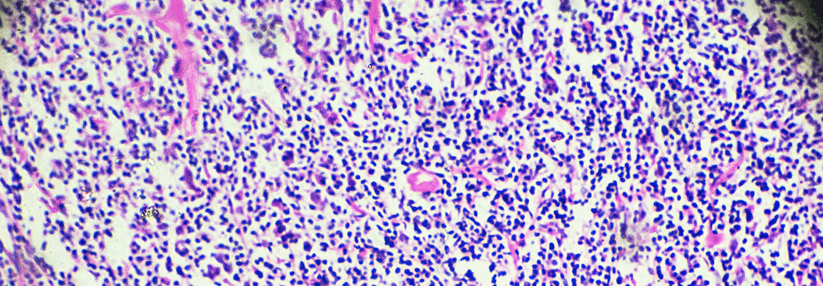

Da mehr als 90 % aller Analkarzinome mit einer Infektion mit humanen Papillomviren (HPV) assoziiert sind, lag der Gedanke an eine der modernen Immuntherapien nahe. Bei metastasierten und fortgeschrittenen Tumoren testeten US-amerikanische Kollegen daher nun den PD-1-Antikörper Nivolumab in einer multizentrischen Phase-II-Studie.

Plattenepithelkarzinome des Analkanals sind selten – mit allerdings weltweit steigender Inzidenz. Durch eine Chemoradiotherapie sind die Tumoren in aller Regel heilbar, solange sie lokal begrenzt sind. Jeder vierte Patient entwickelt aber Fernmetastasen. Für dieses Stadium der Krankheit gibt es bislang keine allgemein akzeptierte Therapie. Eine neue Option, insbesondere bei HPV-assoziierten Tumoren könnten PD-1-Inhibitoren sein.